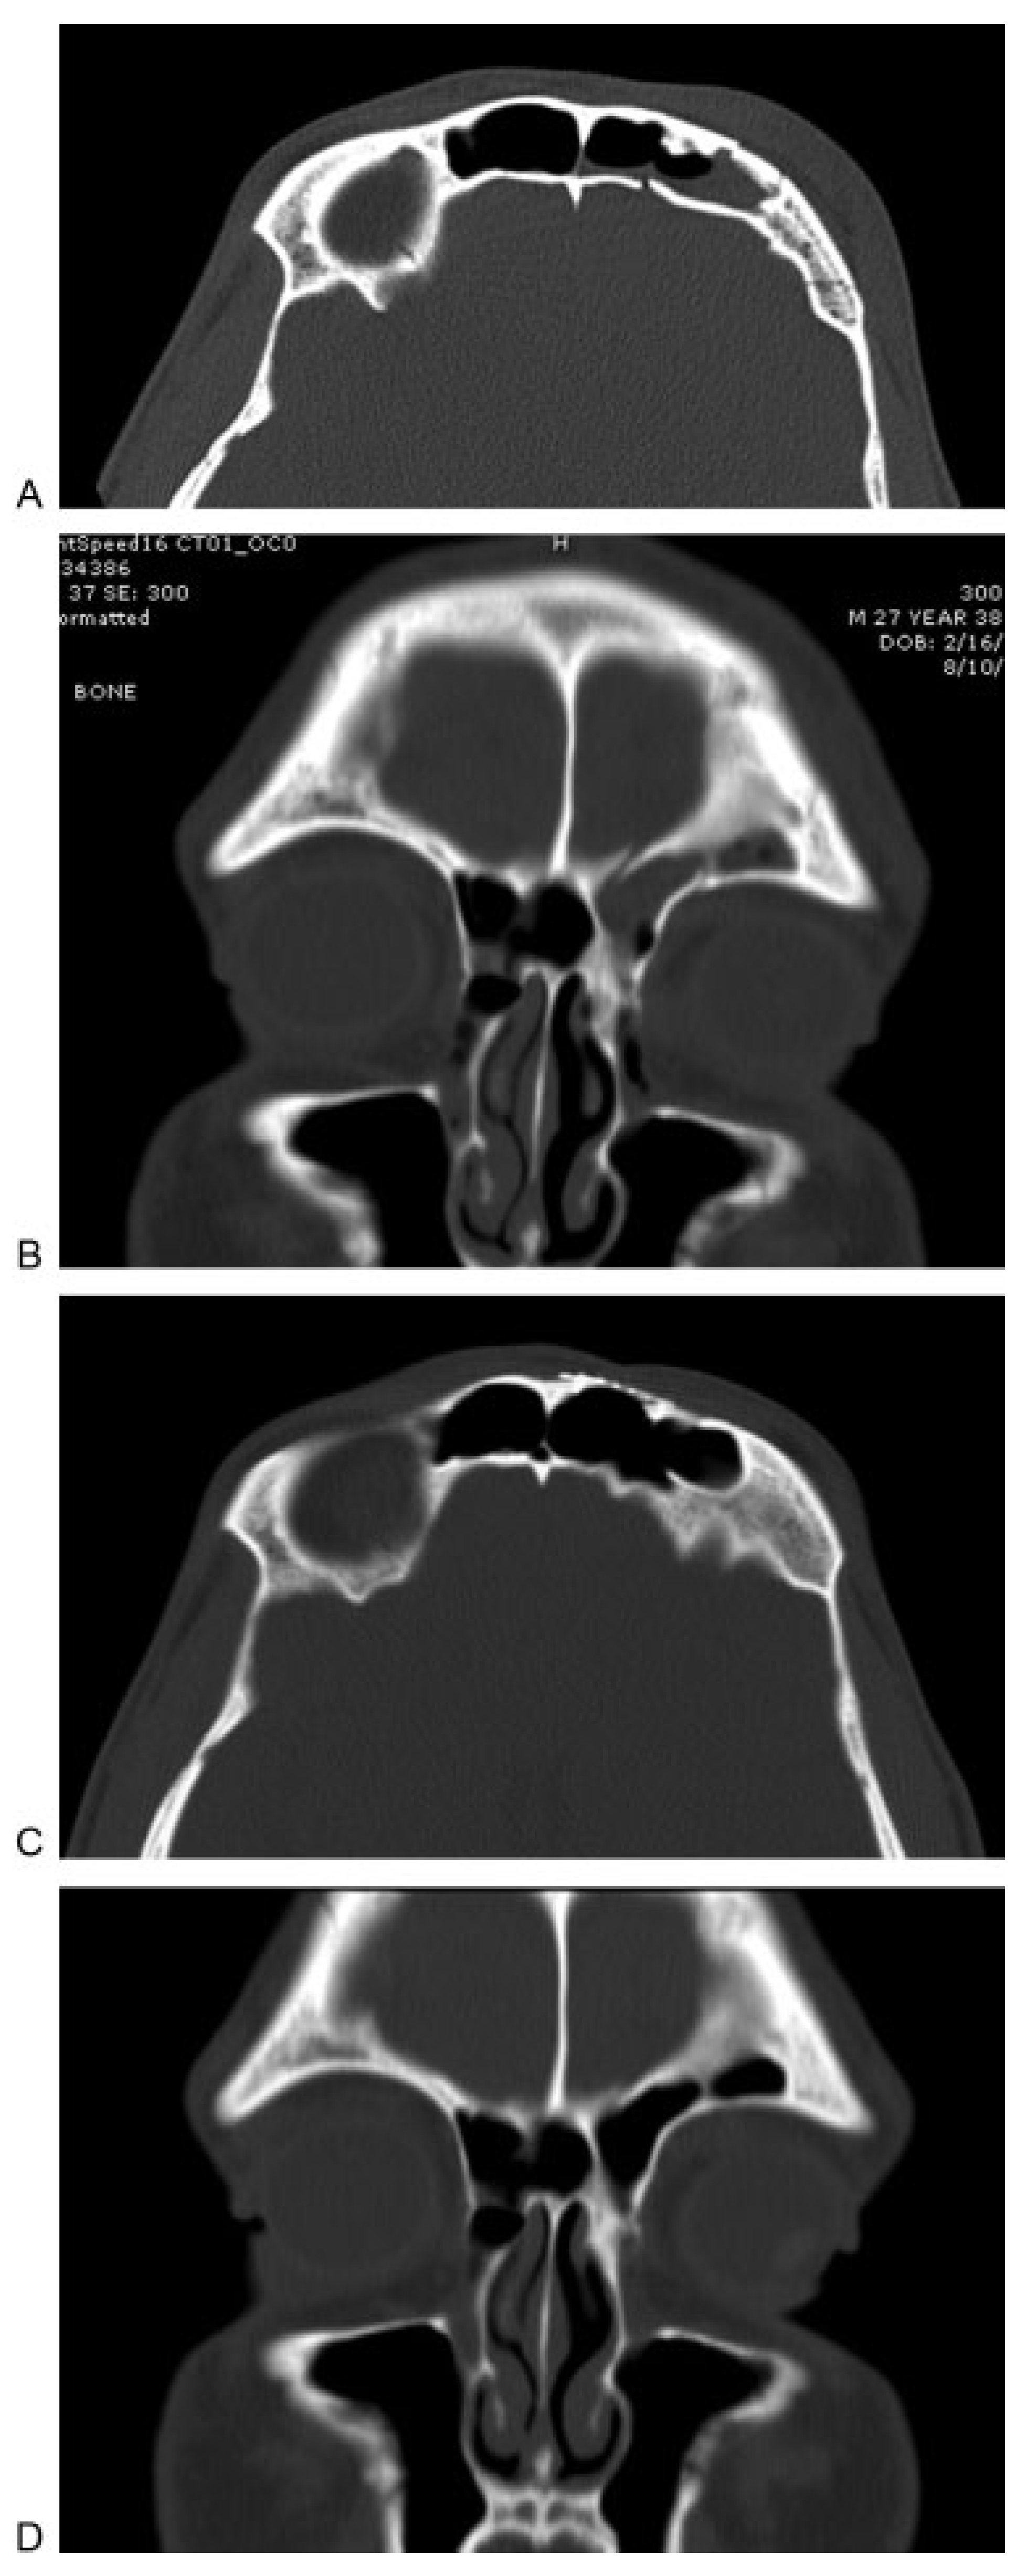

Figure 3.

(A)Axial computed tomographic image showing depression related to an anterior table fracture. (B–E) Intraoperative photographs showing repair of frontal depression related to an anterior table fracture. (B) After making an incision, (C) an endoscope is used to dissect in the subperiosteal plane and expose the depression. (D) Hydroxyapatite cement is then injected and gentle pressure is used to smooth the cement to restore the appropriate contour. (F) Axial postoperative image showing excellent restoration of the frontal contour after placement of bone cement.